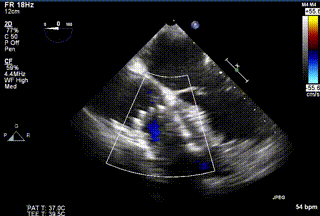

2021年12月24日,復(fù)旦大學(xué)附屬中山醫(yī)院葛均波院士團隊成功應(yīng)用LuX-Valve Plus為一例極重度三尖瓣反流(TR)合并房顫、房缺的患者完成了經(jīng)血管三尖瓣置換術(shù),這是在前基礎(chǔ)上,本周完成的第三例經(jīng)血管三尖瓣置換手術(shù),葛均波院士、周達(dá)新教授等與心外科魏來教授、賴顥教授,心超室的潘翠珍教授、李偉教授及麻醉科的郭克芳教授共同完成了本周手術(shù),均獲得圓滿成功!患者術(shù)后超聲顯示無TR,臨床癥狀明顯改善。本周手術(shù)的成功也為LuX-Valve Plus救治性臨床研究添上了濃墨重彩的一筆。

三例患者入院后,葛均波院士團隊周達(dá)新教授、潘文志教授、張源博士、陳莎莎博士及心超室的潘翠珍教授、李偉教授對患者的情況進行詳細(xì)評估和討論,最終決定為三例患者選擇LuX-Valve Plus40mm、50mm和50mm型號的瓣膜進行手術(shù)治療。手術(shù)后即刻拔除氣管插管,術(shù)后患者三尖瓣反流癥狀得到顯著改善,復(fù)查心超結(jié)果顯示人工三尖瓣瓣膜支架固定穩(wěn)定,瓣葉關(guān)閉形態(tài)未見異常,未見明顯反流。